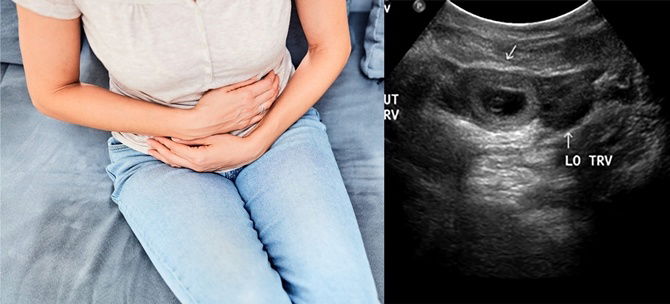

Dalam bahasa Inggeris, istilah ini dipanggil sebagai ectopic pregnancy. Ectopik adalah bermaksud ‘di tempat yang salah’. Dalam kebanyakan kes kehamilan luar rahim, hampir 95 peratus implantasi berlaku dalam tiub fallopian dan sebab itulah ia dikenali sebagai kehamilan tiub (tiub pregnancy).

Apabila ia semakin berkembang berupaya membuatkan ibu berasa sakit dan mungkin mengalami pendarahan. Jika dibiarkan, tiub falopio ini boleh pecah dan menyebabkan pendarahan organ dalaman.

Ia merupakan masalah yang serius dan berpotensi meragut nyawa. Biasanya kehamilan ektopik ini tidak akan bertahan lama kerana ia tidak dapat dialihkan ke dalam rahim dan digugurkan sepenuhnya.